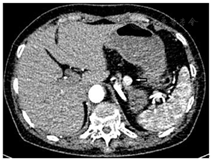

多发性内分泌腺瘤病(MEN)检测:甲状旁腺素(PTH)、胃泌素(Gastrin)阴性,垂体前叶功能正常。胰腺增强CT+灌注:胰体部可见类圆形软组织密度结节影,局部突出胰腺轮廓外,大小约14 mm×11 mm,增强后明显强化,灌注较胰体部正常胰腺组织升高,考虑胰岛素瘤可能大(图1);68Ga-exendin-4 PET/CT:胰体摄取异常增高灶(胰体,大小1.1 cm×1.0 cm,SUVmax 6.4,平均值4.2),为胰升糖素样肽1受体(GLP-1R)过度表达,考虑胰岛素瘤(图2)。

完善患者低血糖症的定位诊断:胰腺灌注CT示胰体部类圆形软组织密度结节影,大小约14 mm×11 mm,增强后明显强化,灌注较胰体部正常胰腺组织升高,68Ga-exendin-4 PET/CT病灶位置与胰腺灌注CT相符,考虑单发胰岛素瘤。